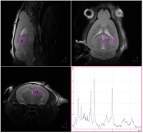

Small Animal Multimodal Imaging

Magnetic Resonance

High Resolution Liquid NMR

High Resolution Liquid NMR High Resolution Magic Angle Spinning (HR-MAS) NMR

High Resolution Magic Angle Spinning (HR-MAS) NMR Time Domain NMR (TD-NMR)

Time Domain NMR (TD-NMR)